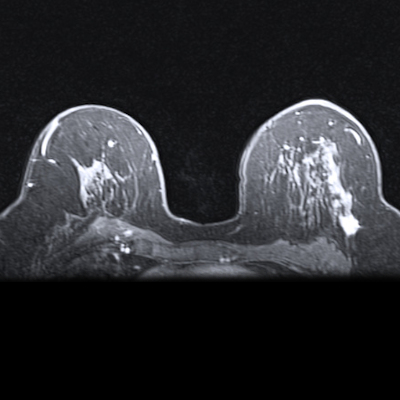

The study is evaluating the potential of Ac-225 alone and with the immunotherapy drug pembrolizumab in women with ER+, HER2-negative, unresectable or metastatic breast cancer expressing somatostatin receptors.